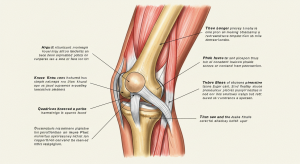

The knee is one of the most complex and largest joints in the body, connecting bones, ligaments, and muscles. Poor habits such as prolonged sitting, lack of exercise, or carrying excess weight place stress on the knees, leading to pain and inflammation. Consistent care through healthy choices helps prevent conditions like arthritis, meniscus tears, and chronic joint stiffness.